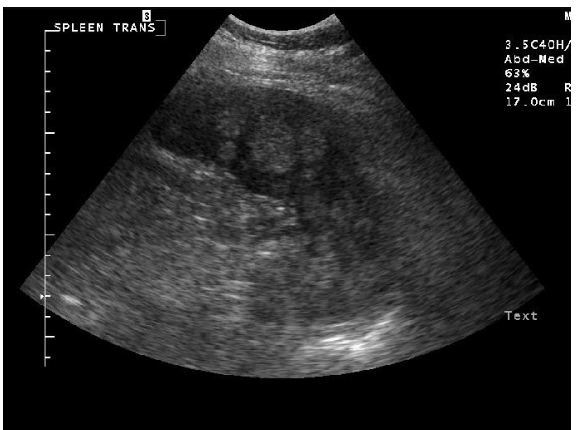

which structure is more hyperechoic on ultrasound: spleen or liver?

spleen

which structure is more hyperechoic on ultrasound: liver or renal cortex?

liver